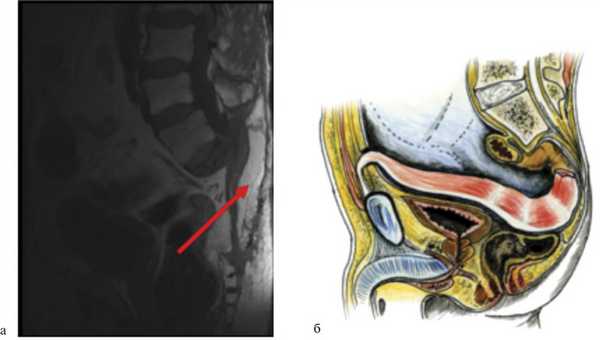

Для лечения подобных осложнений используется метод транспозиции ректоабдоминального лоскута в пресакральную область ректоабдоминальным доступом (рис. 4). Рис. 4. Пример использования метода транспозиции ректоабдоминального лоскута на питательной ножке. а — МРТ больного после операции, сагиттальная проекция. Перемещенный дедерматизированный ректоабдоминальный лоскут указан стрелкой; б — схематическое изображение перемещения лоскута.